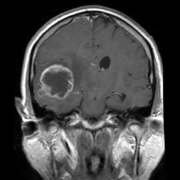

【颞叶胶质瘤案例】9岁,本该是享受童年快乐时光的年龄,然而9岁男孩童童(化名)却只能在病床上度过。童童近半个月来频繁感到头痛,经MRI诊断,右枕颞...